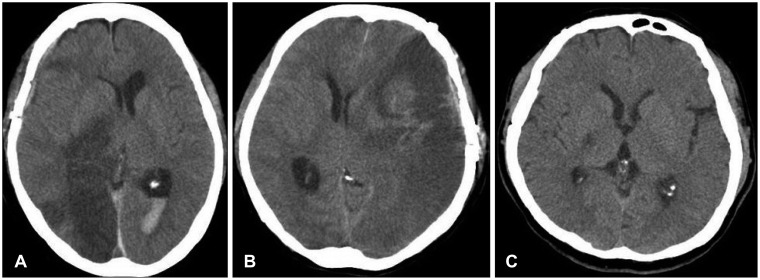

1. 신속한 평가 및 진단: 뇌경색 초기증상과 징후를 신속하게 인식하는 것은 적시에 개입하고 환자 결과를 개선하는 데 필수적입니다. 의료 전문가는 NIHSS(National Institutes of Health Stroke Scale)와 같은 도구를 사용하여 잠재적인 뇌경색 환자를 신속하게 평가하고 컴퓨터 단층 촬영(CT) 스캔 또는 자기 공명 영상(MRI)을 포함한 진단 테스트를 시작하여 진단을 확인하고 유형을 결정해야 합니다.

2. 즉각적인 치료: 뇌경색이 진단되면 뇌 손상을 최소화하기 위해 가능한 한 빨리 치료를 시작해야 합니다. 특정 치료는 뇌출혈 유형에 따라 다릅니다(허혈성 또는 출혈성) 다음과 같이 분류할 수 있습니다.

• 허혈성 뇌졸중(혈전이 뇌로 가는 혈류를 차단하여 발생)의 경우 증상이 시작된 후 처음 4.5시간 이내에 조직 플라스미노겐 활성화제(tPA)와 같은 혈전 용해 약물을 투여하면 결과를 크게 개선할 수 있습니다. 경우에 따라 기계적 혈전 제거술과 같은 혈관 내 절차를 수행하여 혈전을 제거하고 혈류를 회복할 수도 있습니다.

• 출혈성 뇌졸중(뇌 내 출혈로 인해 발생)의 치료는 출혈 조절, 두개골 내 압력 감소, 근본 원인 해결에 중점을 둡니다. 여기에는 혈압을 조절하거나 항응고를 역전시키거나 뇌 부종을 줄이기 위한 약물이 포함될 수 있습니다. 어떤 경우에는 혈액을 제거하거나 손상된 혈관을 복구하기 위해 외과적 개입이 필요할 수 있습니다.